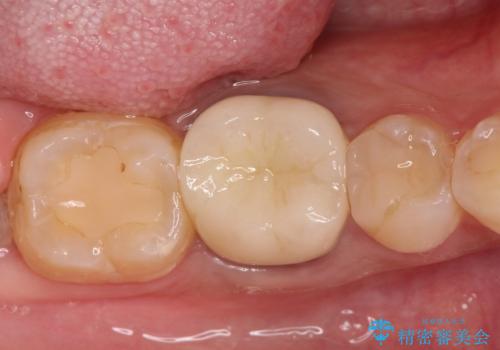

根管治療時に穿孔部位を認め、MTAにて修復し、分岐部の歯周ポケットおよび骨欠損に対しては、再生治療を行うことで、正常な歯周状態の獲得ができました。

歯冠修復はオールセラミッククラウンで行なっております。

今回の症例のように問題点が多い場合は治療期間がかかります。